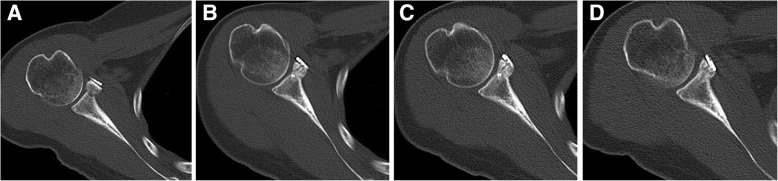

In the axial view at postoperative day 1, grafts in 40 cases (80%) were flush with the glenoid rim, 10 cases (20%) were considered as too lateral, no one case as too medial (Table 3). The ten grafts positioning too laterally were placed higher than the level of glenoid rim with an average of 4.48 ± 0.67 mm (Table 4). However, these grafts became remodeled and the distance higher than the level of glenoid rim decreased to 2.59 ± 0.34 mm, 1.49 ± 0.32 mm and 0.74 ± 0.25 mm at the follow-up of postoperative six months, one year, two years respectively (Figs. 5 and 6) (Table 4). Finally, grafts were flush with the glenoid rim.

Fig. 5.

The remodeling process of grafts positioning too laterally in one case. a In the axial view at postoperative day 1, the graft was placed obviously higher than the level of glenoid rim. b The graft became remodeled and the distance higher than the level of the glenoid rim decreased significantly at postoperative six months. c The graft became further remodeled and nearly being flushed with the glenoid rim at postoperative one year. d The graft was flush with the glenoid rim at postoperative two years without causing any glenohumeral degenerative changes